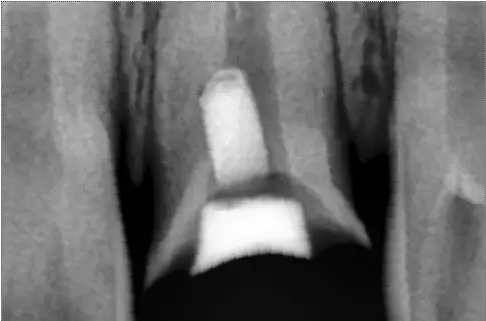

X線片顯示螺紋釘出根管壁

MTA修補(bǔ)后的X片